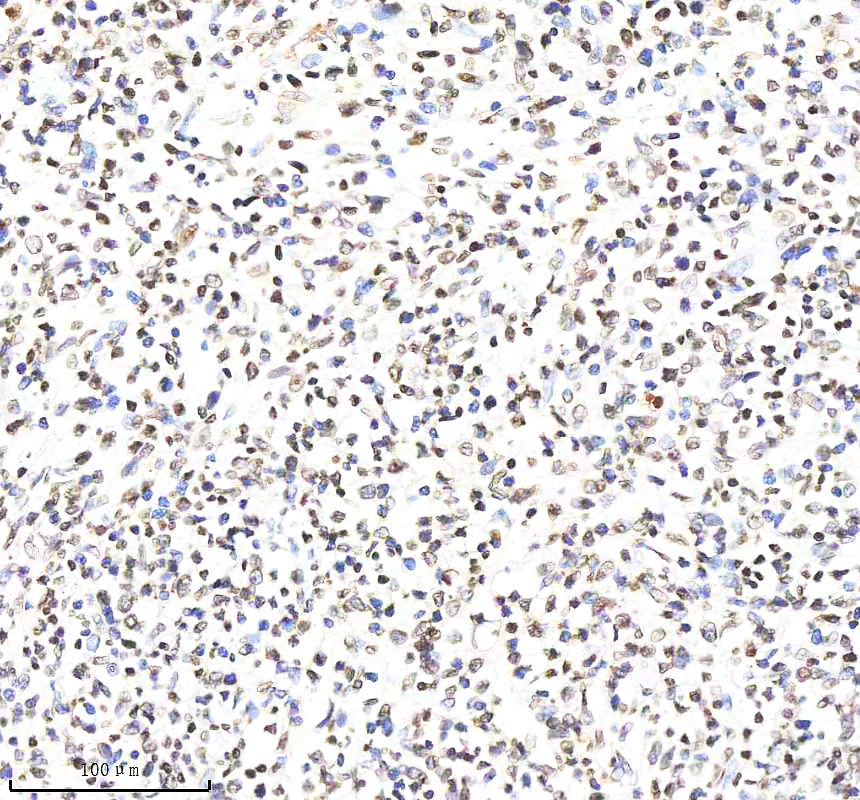

IHC analysis of Histone H4 using anti-Histone H4 antibody (BM4713) .

Histone H4 was detected in a paraffin-embedded section of human B-cell lymphoma tissue. The tissue section was incubated with rabbit anti-Histone H4 Antibody (BM4713) at a dilution of 1:200 and developed using HRP Conjugated Rabbit IgG Super Vision Assay Kit (Catalog # SV0002) with DAB (Catalog # AR1027) as the chromogen.